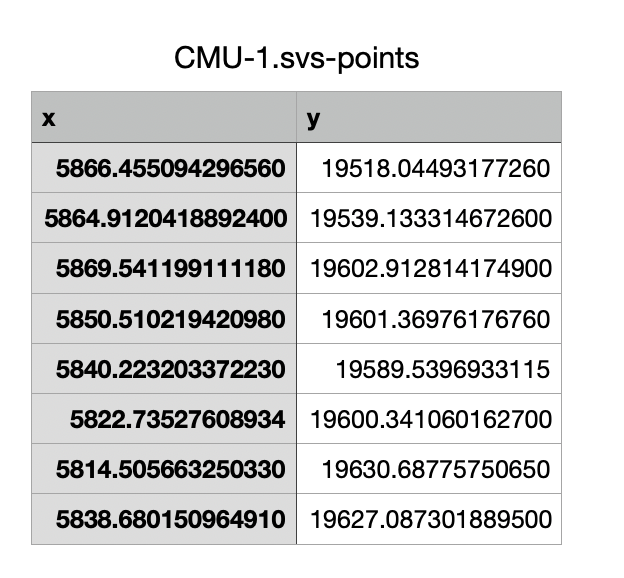

但是,如果您希望将所有点的坐标导出以在其他地方导入,您也可以在计数面板中选择“ Save points”选项。

这将保存坐标以简单的制表符分隔格式,这可能有助于将数据导入到其他软件应用程序中。